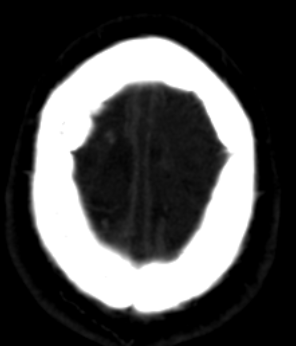

La angiotomografía cerebral evidencia la presencia de múltiples áreas hiperdensas de distribución difusa, bilateral que compromete ambos lóbulos frontales, compatibles con hemorragias intraparenquimatosas de focos múltiples, asociado a edema perilesional (Fig 1 y 2), además se identificó la presencia de signo del delta vacío secundario a trombosis venosa dural que compromete el seno sagital superior, con extensión a la confluencia de los senos, seno transverso derecho, así como el seno yugular y vena yugular ipsilateral (Fig 3 y 4).

FIGURA 3 y 4. angiotomografía cerebral en ventana angiográfica que evidencia en la imagen 3 la presencia del signo del delta vacío y en la figura 4 la presencia del defecto de llenado tras la aplicación del medio de contraste que compromete el seno sagital superior, compatible con trombosis del seno sagital superior.